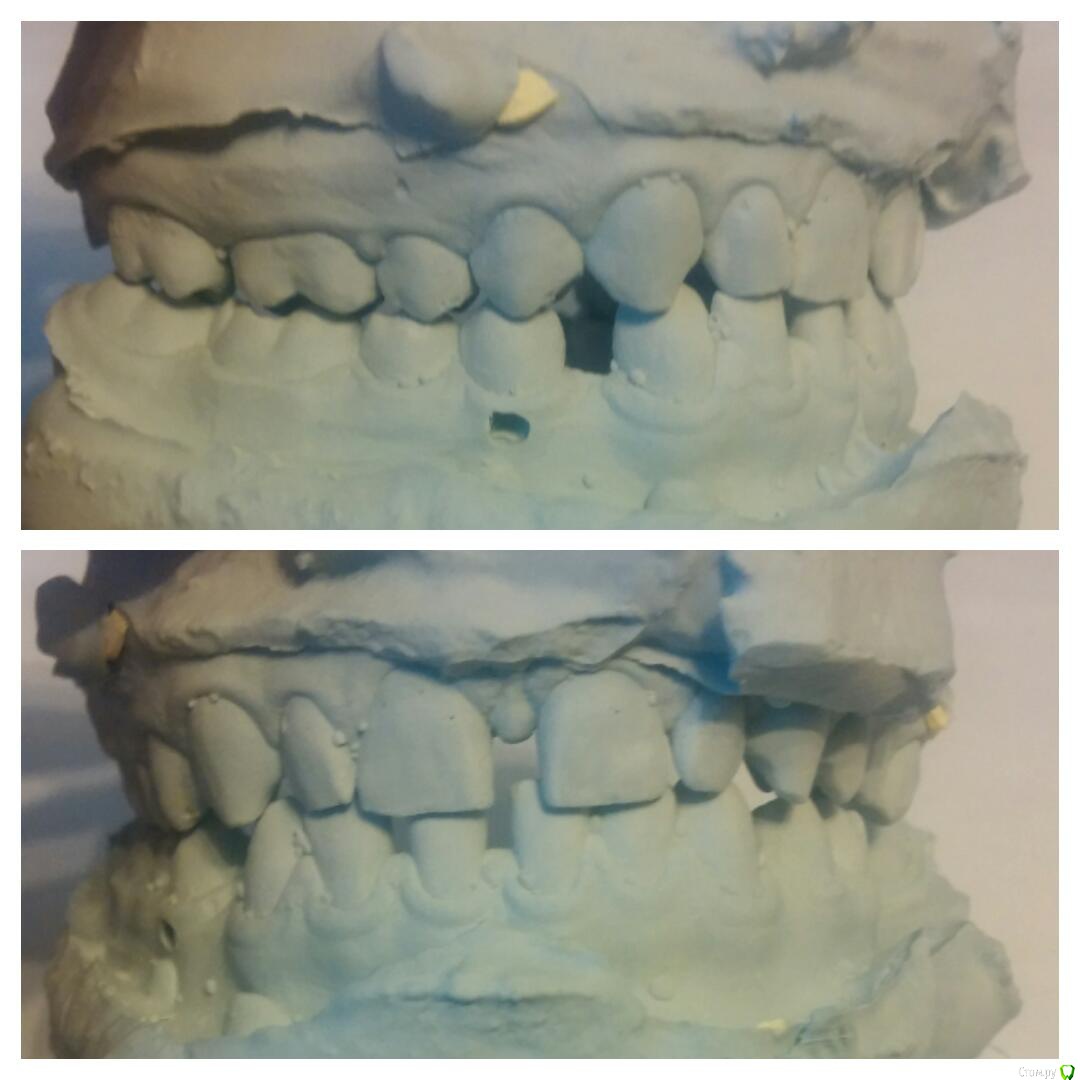

Елена Fy Опубликовано 14 августа, 2015 Поделиться Опубликовано 14 августа, 2015 (изменено) Носила брекеты 1.5 года, сняли месяц назад. Сразу сильно удивил наклон нч вовнутрь, да и верхней тоже. Ортодонт сказала, что это такой прикус и всë нормально. Сейчас ношу капы,но даже в них ВЧ давит на НЧ, есть дискомфорт передних зубов.До брекетов прикус больше устраивал, но смущали щели, вот и пришлось брекеты носить. Подумываю об исправлении прикуса капами.(опять затраты)Подскажите, пожалуйста, может я зря беспокоюсь и это действительно такой прикус? Изменено 14 августа, 2015 пользователем Елена Fy Ссылка на комментарий

Yana guapa Опубликовано 15 августа, 2015 Поделиться Опубликовано 15 августа, 2015 Сразу сильно удивил наклон нч вовнутрь, да и верхней тоже. Ортодонт сказала, что это такой прикус и всë нормально.жалобы на что? п.с. у вас и до лечения нижние зубы были завалены во внутрь. Ссылка на комментарий

Елена Fy Опубликовано 15 августа, 2015 Автор Поделиться Опубликовано 15 августа, 2015 жалобы на что? п.с. у вас и до лечения нижние зубы были завалены во внутрь.Возможно наклон и был, но не такой сильный. По вашему мнению этот прикус в пределах нормы? Меня он лично смущает(( Ссылка на комментарий

Yana guapa Опубликовано 15 августа, 2015 Поделиться Опубликовано 15 августа, 2015 Возможно наклон и был, но не такой сильный. По вашему мнению этот прикус в пределах нормы? Меня он лично смущает((Елена, Вы понимаете, положение и наклон нижних зубов ограничен размером "арки " верхней челюсти. если она у Вас сужена (а Вам в конце лечения именно такой наклон верхних зубов сделали), то и нижний зубной ряд будет сужен, "завален"У многих от природы такой наклон. если не беспокоит - оставляют так. . если есть жалобы - тогда уже исправляют Ссылка на комментарий